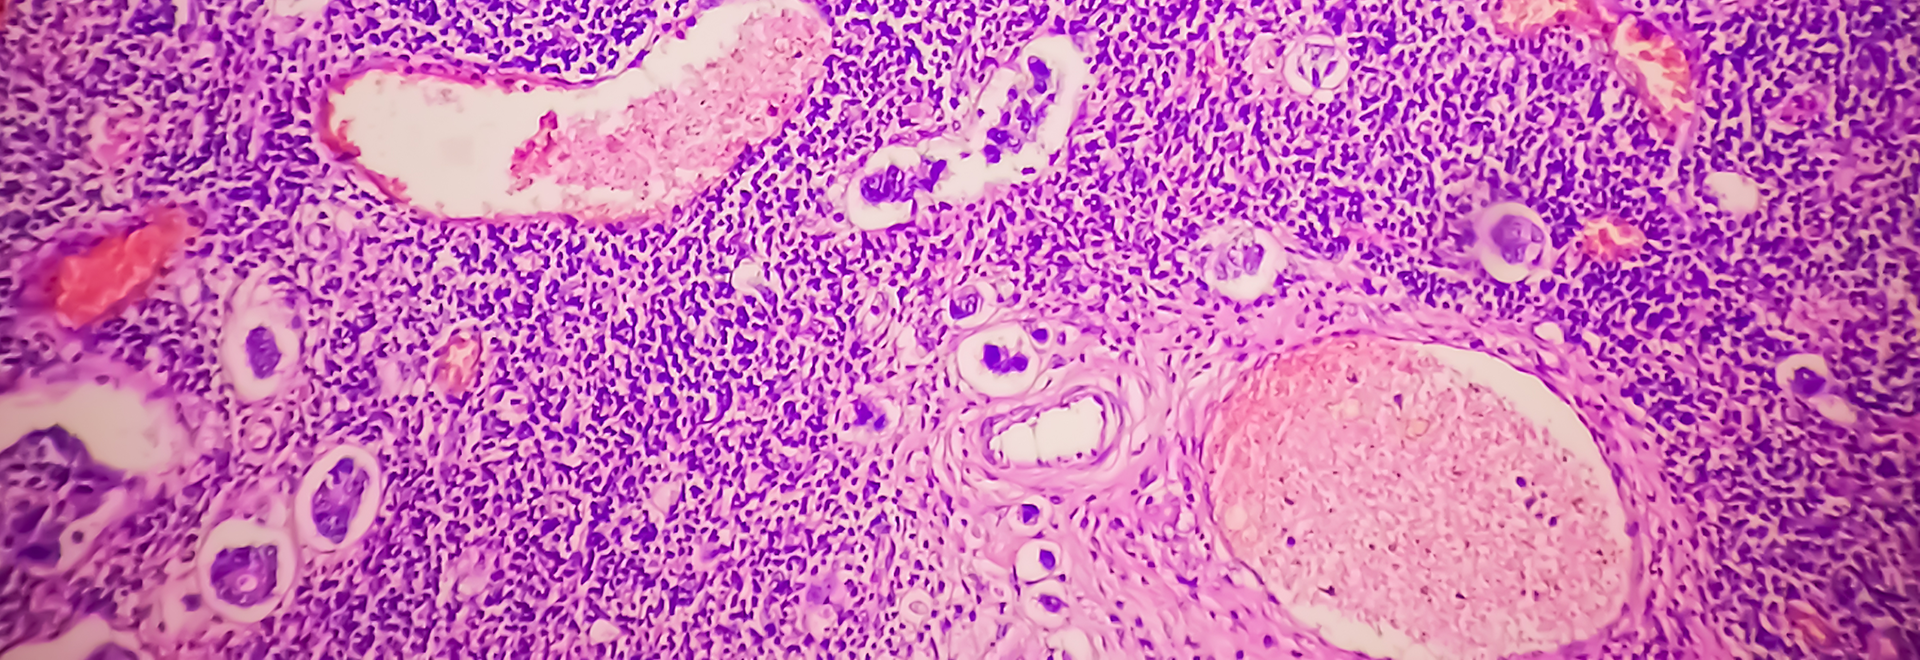

Our main goal is to understand how normal cells change to become cancerous and how cancer cells grow and spread to form metastatic lesions.

The Breast Cancer Cell Biology Group examines molecular pathways which control responses of breast cancer cells to various extracellular stimuli. We are specifically focused on regulation signalling via cell adhesion proteins of integrin superfamily and receptor tyrosine kinases.

Expression levels of various tetraspanin proteins and composition of TERMs are changed during the metastatic progression in breast cancer. We found that clustering of transmembrane proteins within TERMs and tetraspanin-dependent recruitment of cytoplasmic proteins to these microdomains coordinates a diverse range of signalling pathways which control behaviour of breast cancer cells.

We use various breast cancer model systems by growing human breast cancer cells in three dimensional extracellular matrix (3-D ECM) in combination with other cell types to mimic the effect of tumour microenvironment. We developed specialised imaging and biochemical approaches to analyse the role of tetraspanins in signalling in breast cancer cells cultured in 3D ECM.